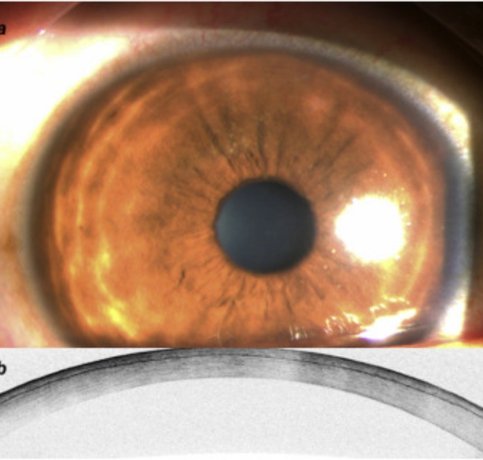

Laser Refractive Surgery is a minimally invasive procedure that reshapes the cornea using advanced laser technology to correct refractive errors. By precisely altering the corneal curvature, it allows light to focus accurately on the retina, resulting in clearer vision without corrective lenses. Modern advancements like LASIK, SMILE, and PRK ensure faster recovery, high precision, and minimal discomfort – making laser vision correction a safe and effective solution for a wide range of patients.

LASIK (Laser-Assisted In Situ Keratomileusis)

SMILE (Small Incision Lenticule Extraction)

PRK (Photorefractive Keratectomy)

Surface laser treatment for thin corneas or specific cases.